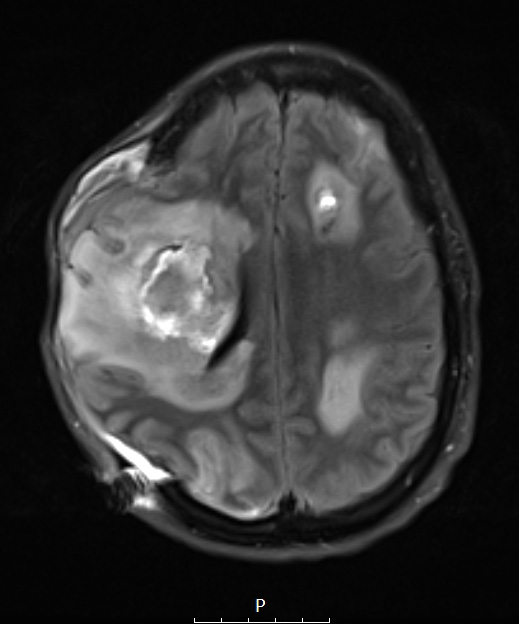

This FLAIR scan shows the largest lesion with marked edema, which is present around smaller lesions as well.